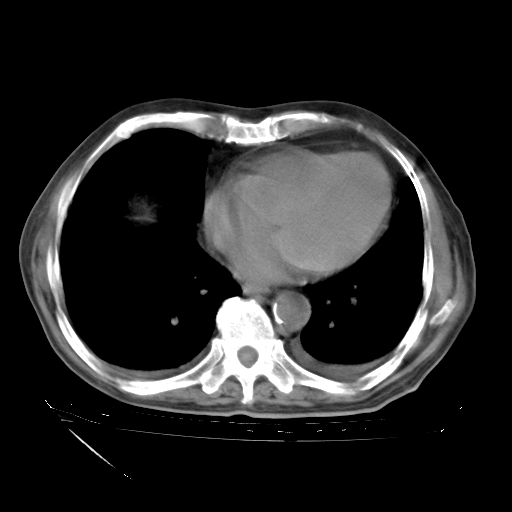

经过24天治疗,岳父的病情基本稳定。生活基本可以自理,可以下床活动。呼吸困难早已消失。体温基本正常。

主要治疗甲强龙80mg×14天,60mg×10天;同时抗结核(异烟肼+利福平+乙胺丁醇)。环磷酰胺0.1 tid 10天。

特别感谢胡教授、高管、桃子版主给出关键的治疗建议。桃版把所有肺部影像和全部临床资料请所在医院呼吸科、感染病科、结核科、临床免疫科专家会诊。临床免疫科专家制定了完整的治疗方案。